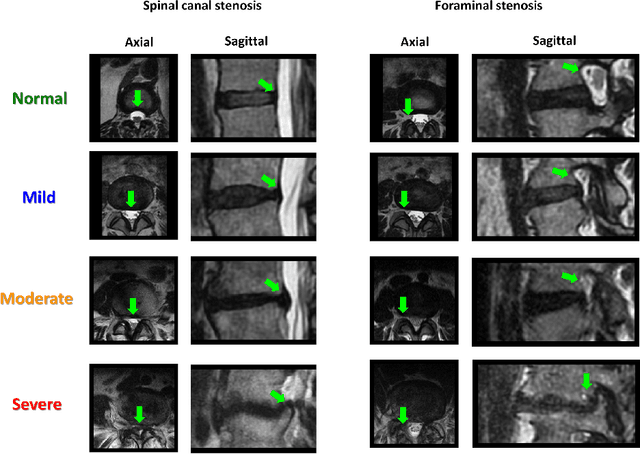

Abstract:The high prevalence of spinal stenosis results in a large volume of MRI imaging, yet interpretation can be time-consuming with high inter-reader variability even among the most specialized radiologists. In this paper, we develop an efficient methodology to leverage the subject-matter-expertise stored in large-scale archival reporting and image data for a deep-learning approach to fully-automated lumbar spinal stenosis grading. Specifically, we introduce three major contributions: (1) a natural-language-processing scheme to extract level-by-level ground-truth labels from free-text radiology reports for the various types and grades of spinal stenosis (2) accurate vertebral segmentation and disc-level localization using a U-Net architecture combined with a spine-curve fitting method, and (3) a multi-input, multi-task, and multi-class convolutional neural network to perform central canal and foraminal stenosis grading on both axial and sagittal imaging series inputs with the extracted report-derived labels applied to corresponding imaging level segments. This study uses a large dataset of 22796 disc-levels extracted from 4075 patients. We achieve state-of-the-art performance on lumbar spinal stenosis classification and expect the technique will increase both radiology workflow efficiency and the perceived value of radiology reports for referring clinicians and patients.